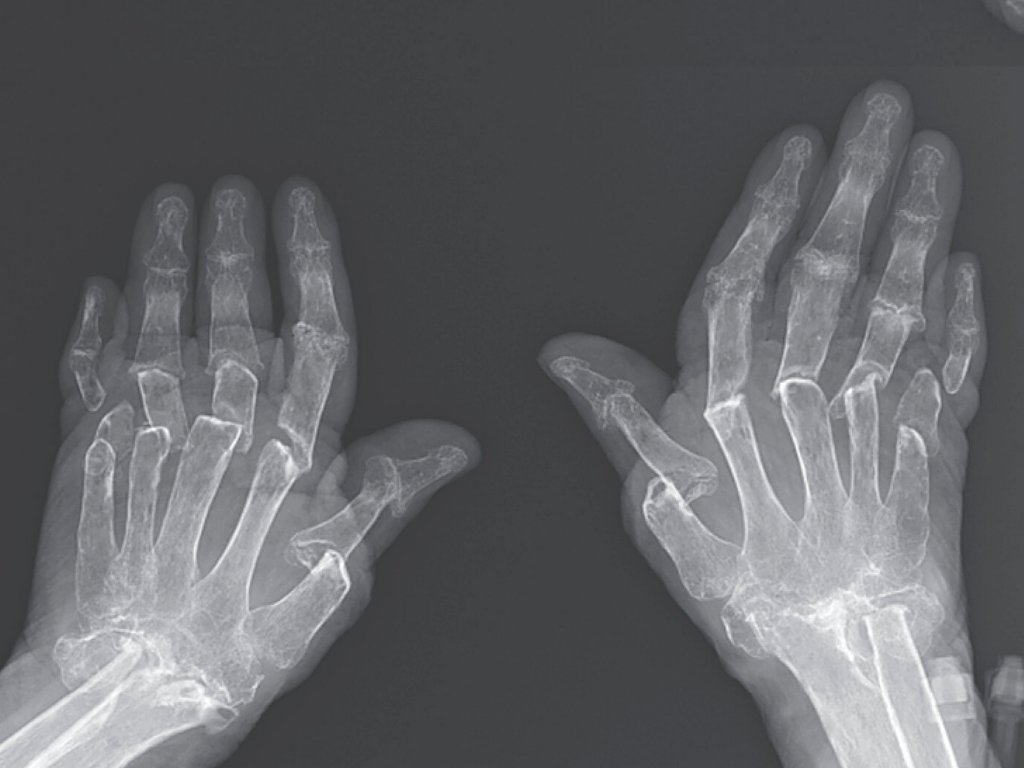

تسببت إحدى الحالات الصحية النادرة في "اختفاء" العظام من أصابع امرأة وانكماشها، وفقا لما ذكره تقرير نشر حول حالتها.

وأدت الحالة النادرة إلى فقدان العظام للترابط في يد المرأة البالغة من العمر 69 عاما، وهي حالة تعرف باسم "التهاب المفصل الجادع" (telescoping fingers).